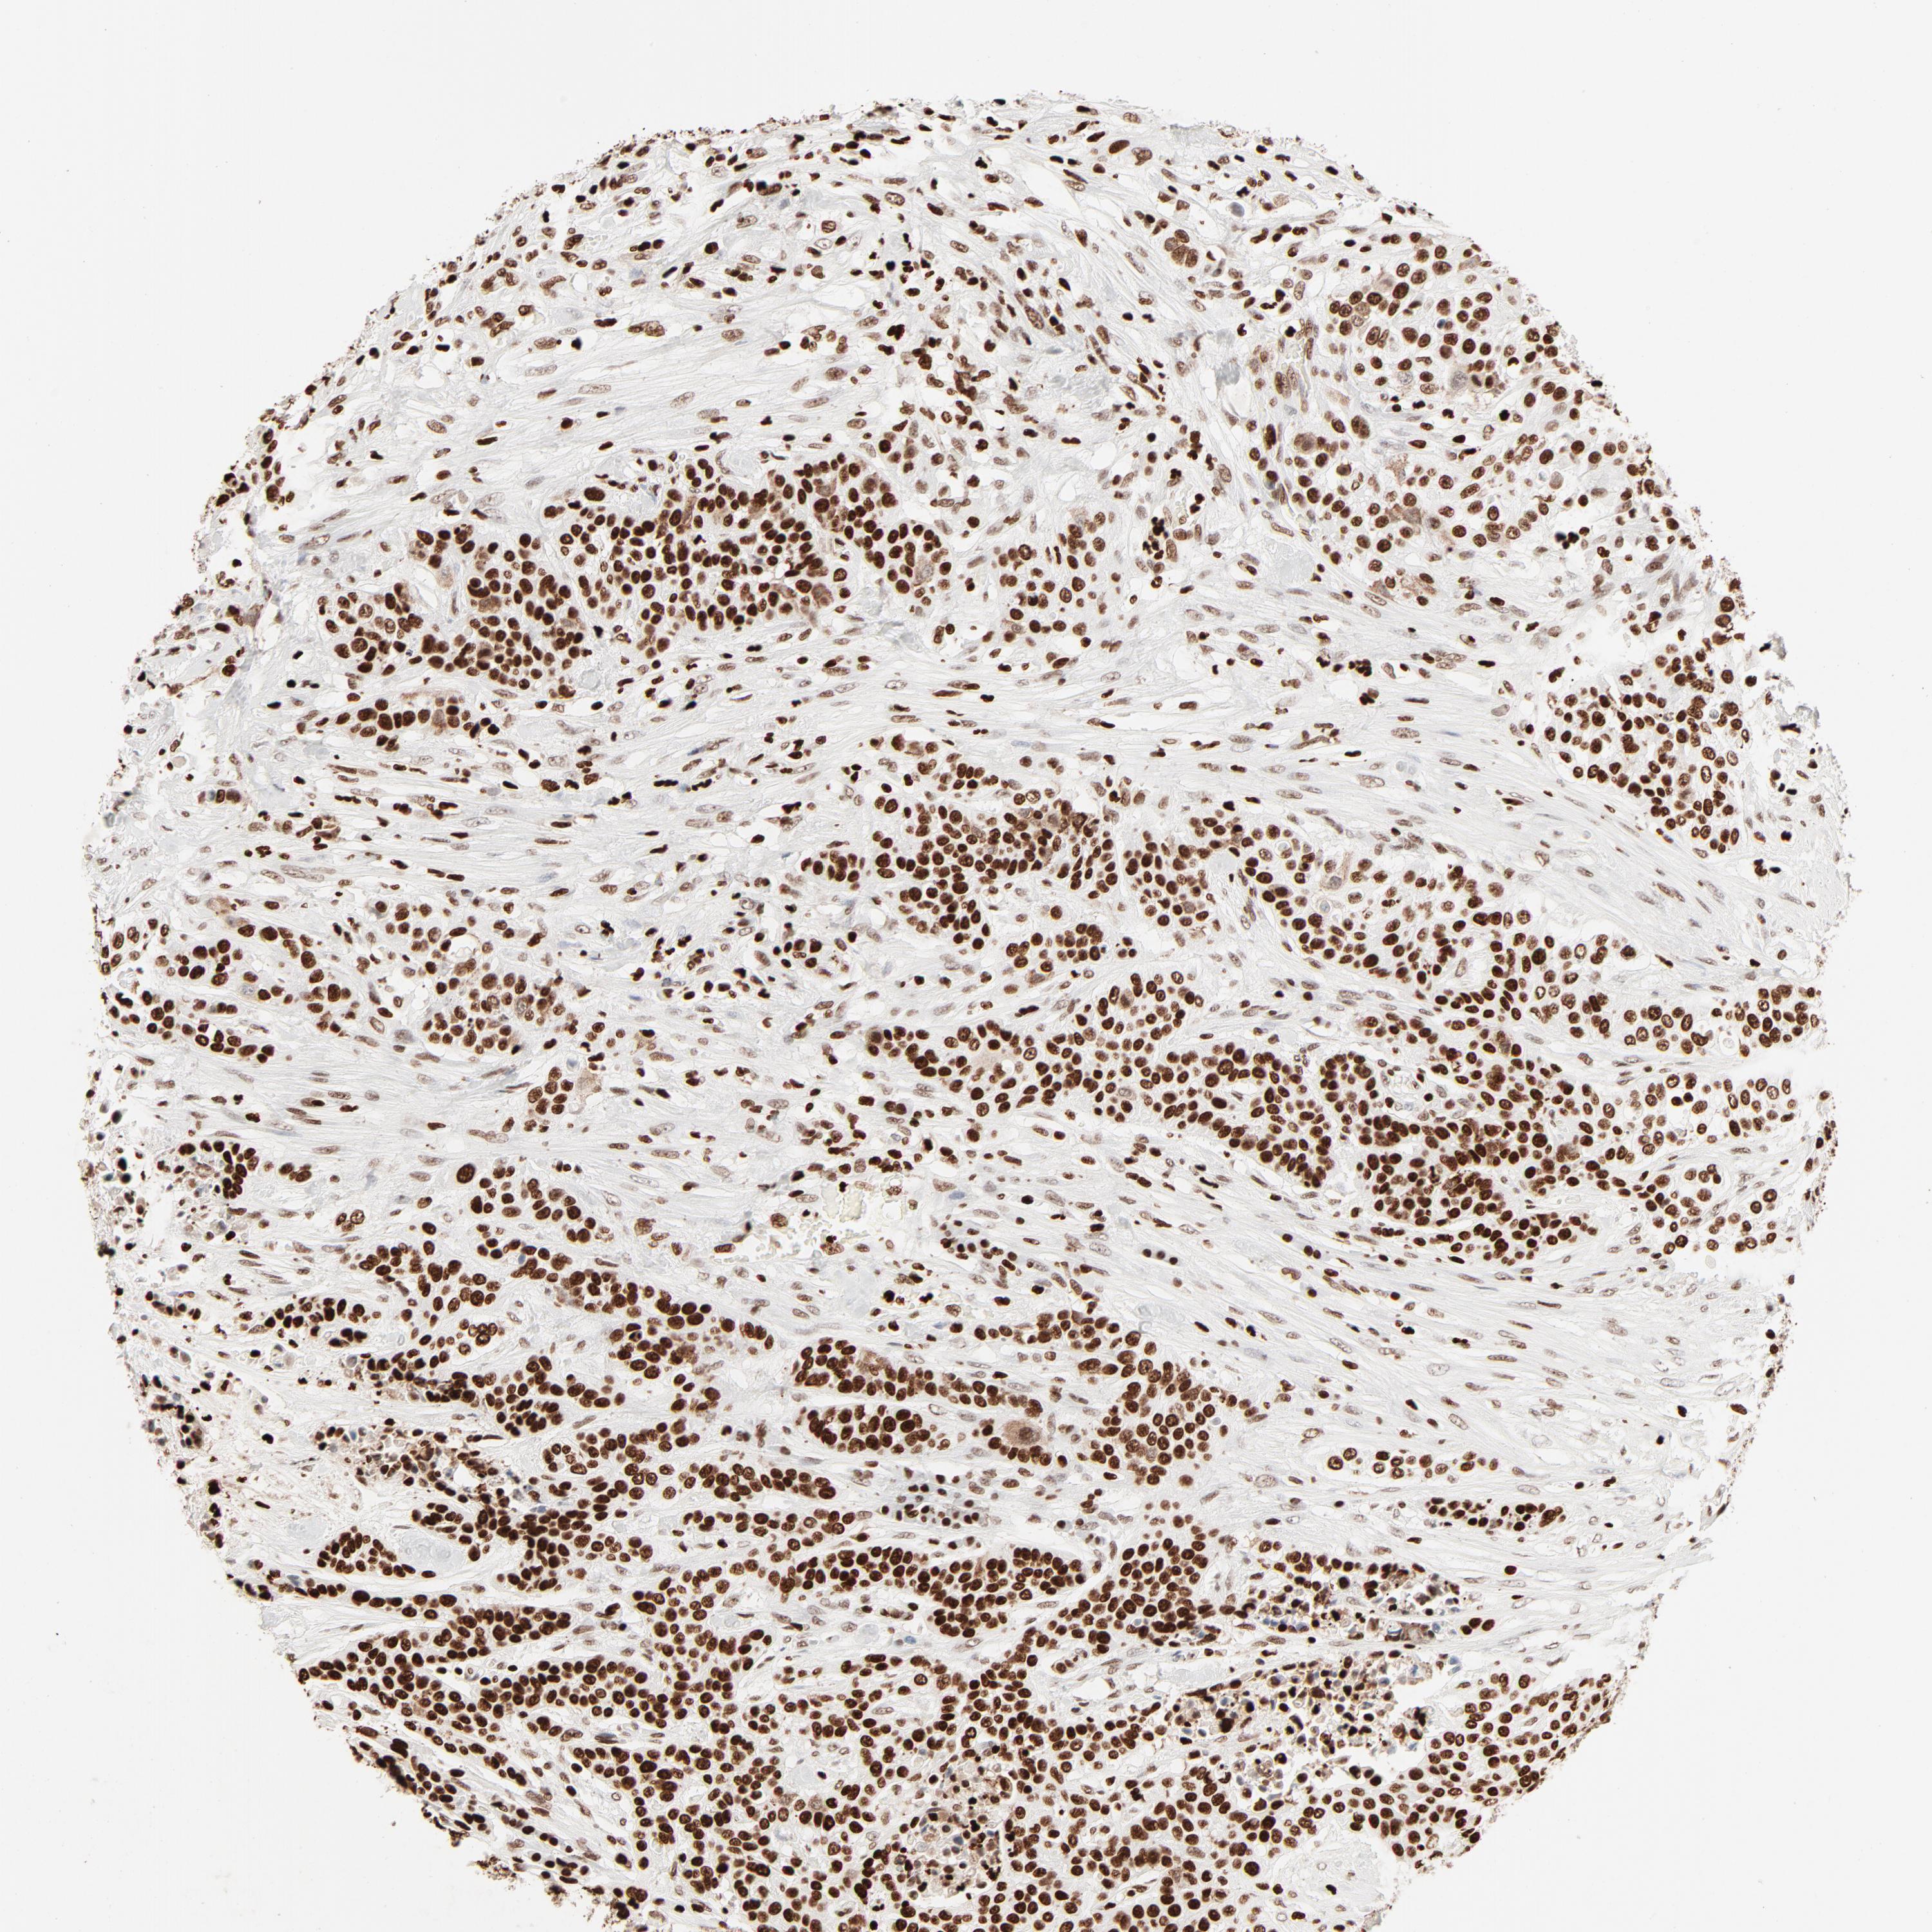

UROTHELIAL CANCER - Protein expressioni

A mouse-over function shows sample information and annotation data. Click on an image to view it in a full screen mode. Samples can be filtered based on level of antibody staining by selecting one or several of the following categories: high, medium, low and not detected. The assay and annotation is described here.

Note that samples used for immunohistochemistry by the Human Protein Atlas do not correspond to samples in the TCGA dataset.

Antibody stainingi

Antibody staining in the annotated cell types in the current human tissue is reported as not detected, low, medium, or high, based on conventional immunohistochemistry profiling in selected tissues. This score is based on the combination of the staining intensity and fraction of stained cells.

Each image is clickable and will lead to virtual microscopy that enables deeper exploration of all samples and also displays staining intensity scores, fraction scores and subcellular localization as well as patient and tissue information for each sample.

Antibody HPA003506

Antibody CAB005873

Urothelial carcinoma, High grade

Urothelial carcinoma, Low grade